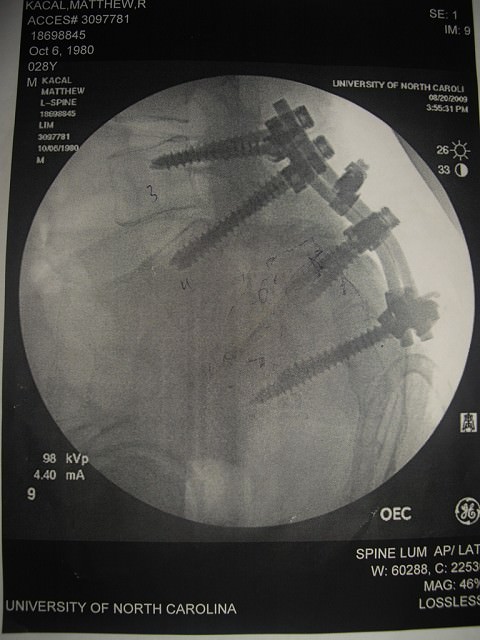

I want to post a picture of his back… Matthew will look at it and say:

“Isn’t it amazing how God put me back together?”

I think this x-ray shows how God has placed him back together through the hands of his people.  Dr. Lim said that he had a millimeter one either side of the screw before he would hit nerves.  I stand in aww of how present God was during Matthew’s 8-9 hours surgery.  God was there each and every moment.  Being far from home, God placed in the hands of a caring surgeon, one who even called Matthew at home to check on him.  And more importantly, God took Matthew in His hands and continues to care for him each and every day.